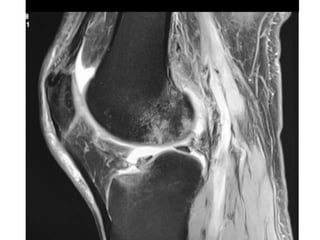

The document presents a detailed case study of a patient with transient osteoporosis of the hip (TOH) and spontaneous osteonecrosis of the knee (SONK) treated at Choithram Hospital & Research Centre in India. Over 20 years, the patient experienced multiple episodes of TOH and SONK with no history of trauma or co-morbidities, resulting in resolutions and recurrences of conditions. The information is intended for orthopedic surgery students and highlights personal experiences and case collections, with a disclaimer regarding content usage and potential controversies.